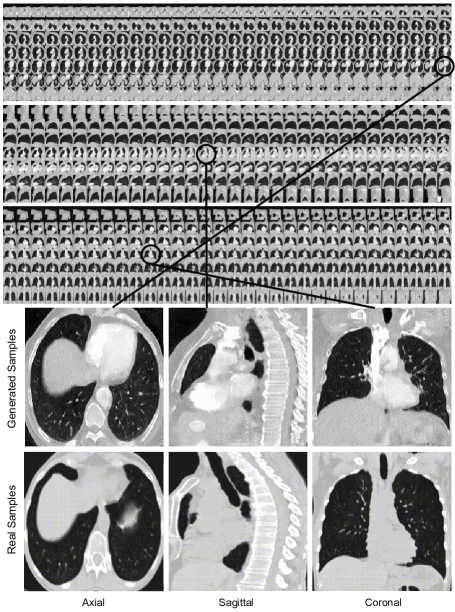

The evaluation of the generated CT-scans was designed to be done under two scrutinies: (1) qualitative inspection of the generated volumes from CT-SGAN where the diverse variation and consistency across all three views of axial, coronal, and sagittal were met (2) quantitative demonstration that synthetic data from CT-SGAN are valuable to build deep learning models for which limited training data are available. We evaluate the efficacy of data augmentation by three nodule detection classifier experiments (i) training with only real dataset (ii) training with only 10,000 synthetic volumes (iii) training with 10,000 synthetic volumes as a pretraining step and then continue to train on the real dataset (i.e., fine-tuning).

The visual qualitative evaluation of the generated volumes was studied based on three criteria: (1) Anatomical consistency of the generated slices, (2) Fidelity of generated slices to the real ones, and (3) diverse generation of CT-scans. Regarding the first two, Figure 1 shows these requirements were met as in thousand of generated CT-scans we rarely noticed any anomalies. For the high quality of the slices and slabs, we observed consideration of 3D slices and the inclusion of both patient- and slice-specific noises played important roles. As to the diversity in the generated CT-scans, i.e. to avoid mode collapse, and also to ensure stability in training, the discriminators’ losses contained the gradient penalty discussed in [15] introducing variations in the generated volumes. While CT-SGAN was preferably trained with Wasserstein loss [1], we did not notice a drastic change when the vanilla Jensen-Shannon loss was employed. Also, even though artifacts could appear in the generated CT-scans, the presence of them was partially related to the noise in real CT-scans produced by scanners.